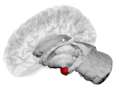

لوزة المخ amygdalaecorpus amygdaloideum؛ باللاتينية، من اللاتينية ἀμυγδαλή, amygdalē، 'almond', 'tonsil'[1])، مدرجة في تشريح گراي باسم nucleus amygdalæ، هي مجموعتين من النوى على شكل لوزة تقعان في المنطقة العميقة والوسطى داخل الفص الصدغي في المخ لدى الثدييات المتطورة، ومنها البشر.[2] أظهرت الأبحاث أن للوزة المخ دوراً أساسياً في معالجة الذاكرة، صنع القرار، وردود الفعل العاطفية، وتعتبر لوزة المخ جزءاً من الجهاز الحوفي.[3]

تشكل لوزة المخ جزءاً من الجهاز الحوفي، وتشارك في إدراك وتقييم العواطف والمدارك الحسية والاستجابات السلوكية المرتبطة بالخوف والقلق وهي تراقب باستمرار ورود أي إشارات خطر من حواس الإنسان تعتبر كنظام إنذار واستشعار للمتعة.